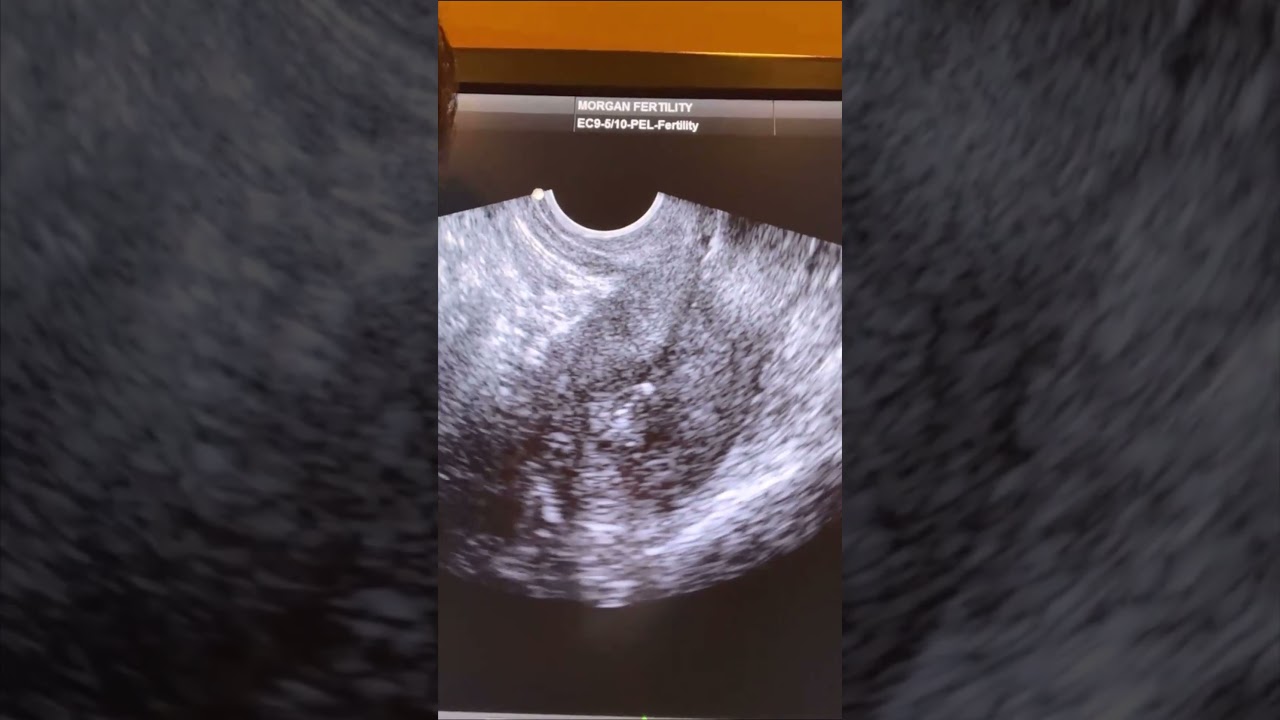

Ivf Embryo Transfer Ivf Embryo Transfer Process Indira Ivf An embryo transfer is the final step of ivf. here we will explore all the different types, what to expect, success rates, costs, risks, and more. Embryo transfer is the final step in the ivf process. details about ultrasound guidance for ideal embryo placement are explained with video and pictures. Are you considering a fresh embryo transfer for your next round of in vitro fertilization (ivf)? if you have some questions about the process, you are not alone. this guide will help you understand everything you need to know about fresh transfers. what is a fresh embryo transfer?. This guide will help you to understand the different stages of ivf treatment, including medicines, risks and side effects, egg collection, fertilisation and embryo transfer. Watch an embryo transfer procedure as seen on scan. this is what we, the fertility specialists and the mums, see on scan. in this video: ***catheter. Embryo transfer is considered the final step of ivf treatment. this procedure involves inserting embryos created in the laboratory into the womb of the recipient woman.

Ivf Embryo Transfer Stock Image M802 0125 Science Photo Library Watch an embryo transfer procedure as seen on scan. this is what we, the fertility specialists and the mums, see on scan. in this video: ***catheter. Embryo transfer is considered the final step of ivf treatment. this procedure involves inserting embryos created in the laboratory into the womb of the recipient woman.